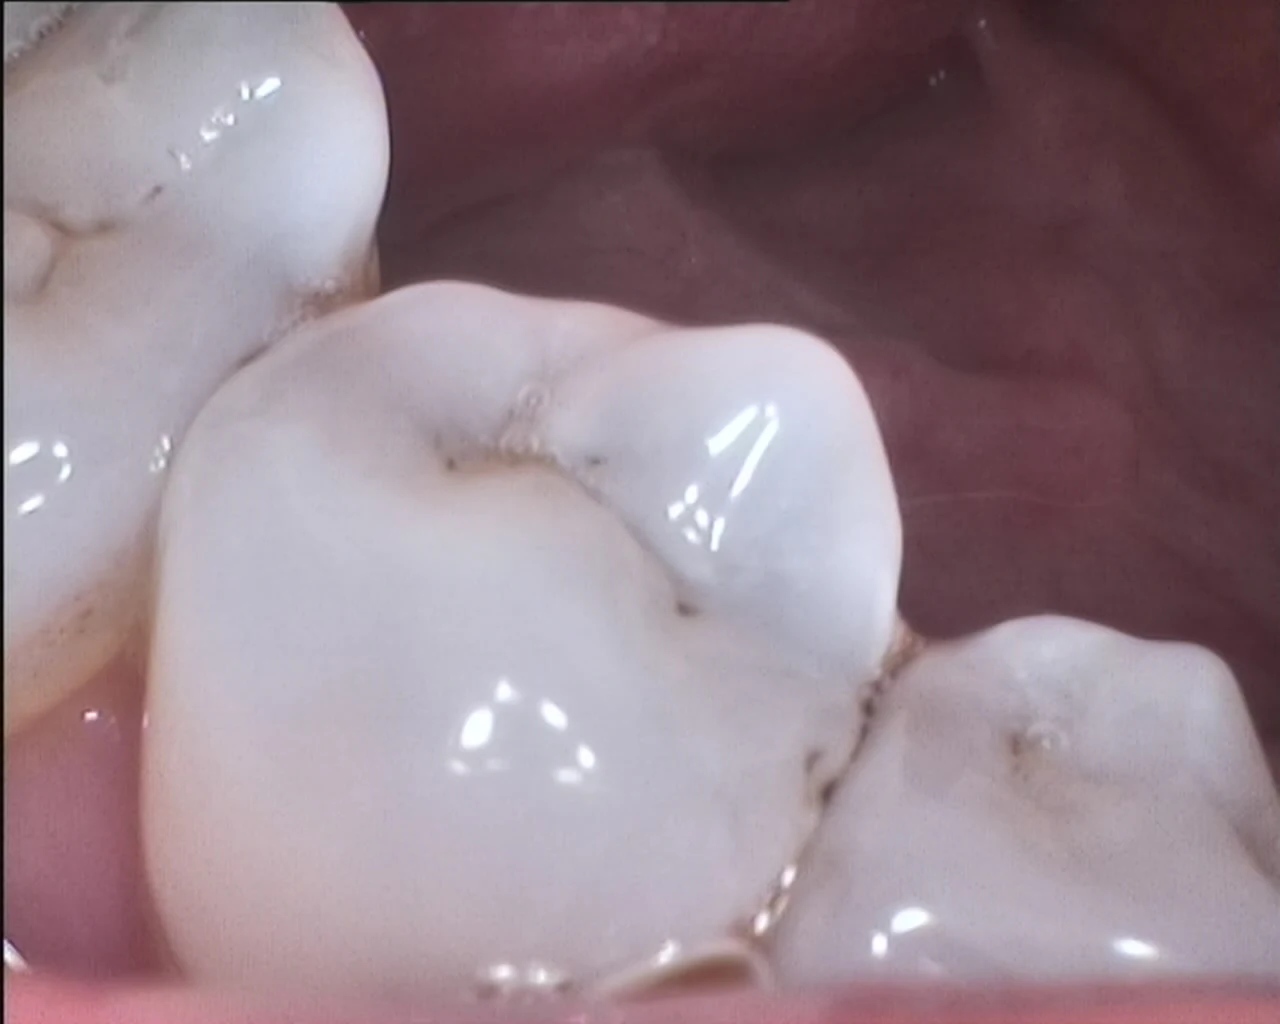

2.0 Mega Pixels MD-2000A

* 1/4“ CCD* 2.0 Mega pixelas.

Details Images